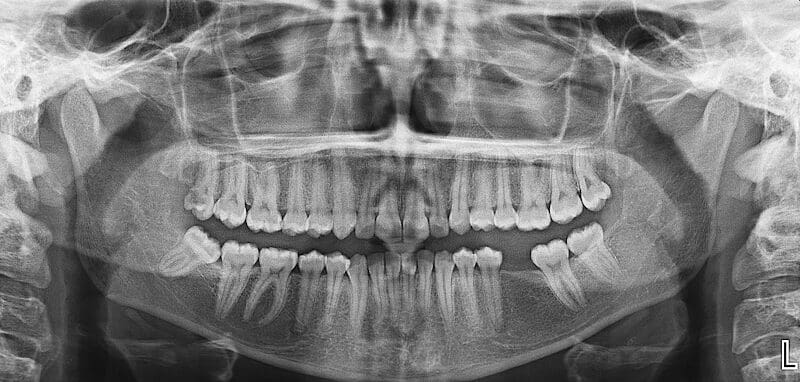

Imagenes Digitales (San Cristobal) es un establecimiento de Dentista ubicado en Santiago Rodríguez, Republica Dominicana. Brinda servicios de salud dental, limpiezas, extracciones, ortodoncia, blanqueamiento. Ideal para residentes y turistas que buscan Dentista en Republica Dominicana.